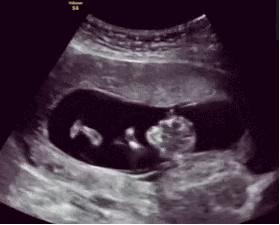

依依是个准妈妈,已经怀孕7个月了,刚怀孕时她就辞掉了工作,安心在家待产,而婆婆也特意从乡下老家赶来照顾依依。

这天依依和老公正坐在沙发上看电视,孕妈突然摸着肚子说:“老公,你快摸摸,娃在动呢,还是踢得我左边!”

老公摸完表示:“咱家宝宝莫不成是个左撇子?怎么总喜欢待在左边呢?”而正站在餐厅收拾的婆婆听到后,非常高兴地走过来说道:“宝宝一个是男娃娃!”

依依和老公一脸懵,婆婆连忙解释,民间都说左边胎动的男孩,所以依依肚子里肯定是个男宝。

而准妈妈和老公就非常默契地笑了笑,什么都没说。后来依依顺利生下一名女宝,婆婆同样很喜欢,不过就是再也没提左边胎动的事了~